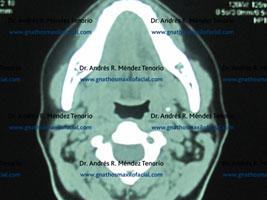

Imágenes de control confirmando la eliminación completa de la lesión